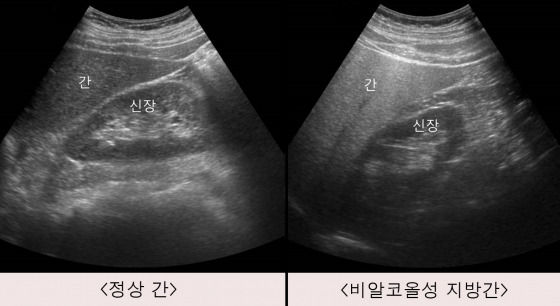

| 지방간 없애는 법 총정리 (생활습관만 바꿔도 충분합니다) (1) | 2026.01.06 |